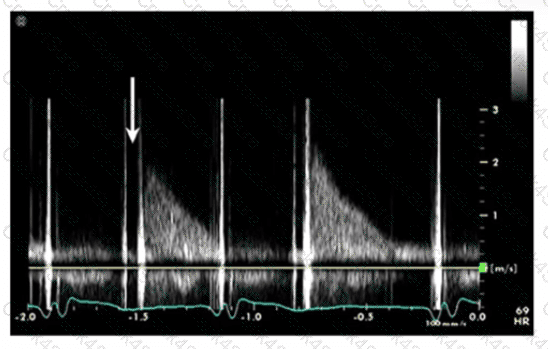

Which is the most likely abnormality represented in these images from a 48-year-old man with shortness of breath?

Which diagnosis is most consistent with the findings in these images?